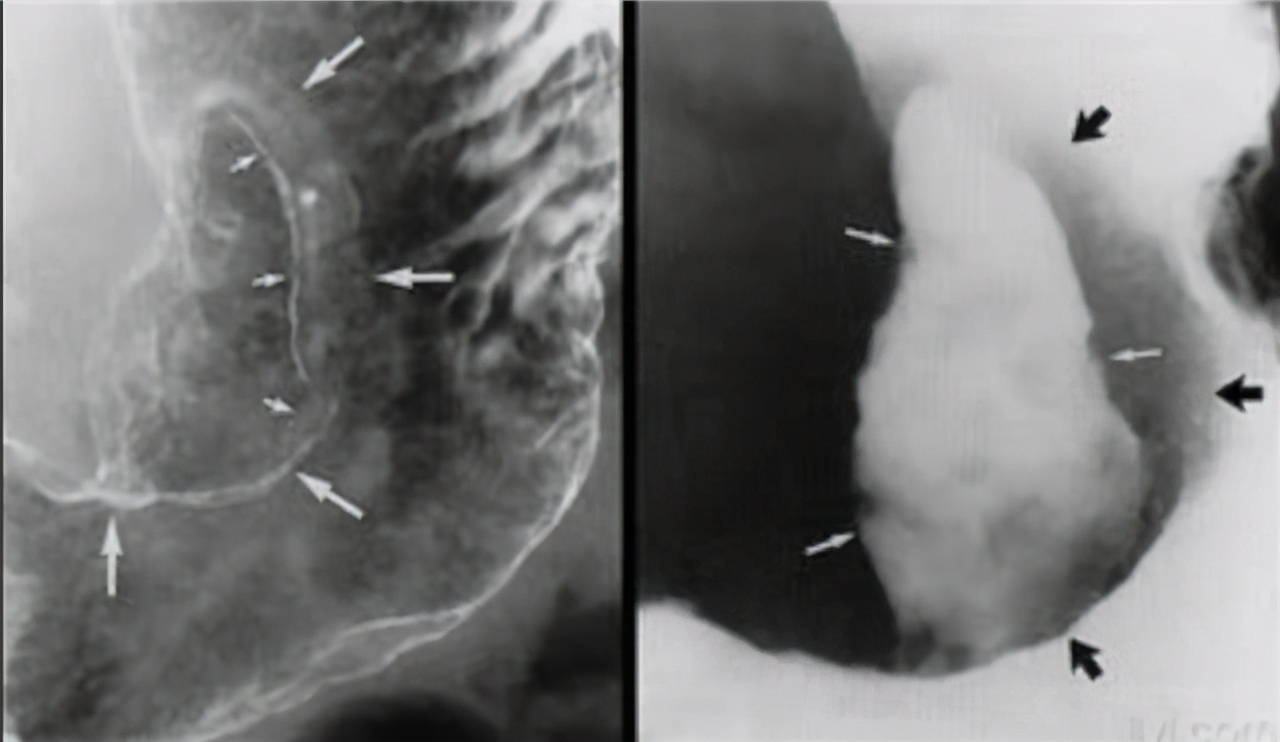

●第一阶段,慢性浅表性胃炎转变为萎缩性胃炎;

●第二阶段,萎缩性胃炎转变为肠上皮化生和轻,中度不典型的增生;

●第三阶段,肠上皮化生和轻,中度不典型的增生转变为重度不典型的增生;最后阶段,由重度不典型增生转变为最终的胃癌。

其中,增生可以分为低级别和高级别的异性增生,转变为癌症的概率为0~23%和60~85%,所以低级别常常进行胃镜检查,高级别需要进行预防性的胃镜下治疗。